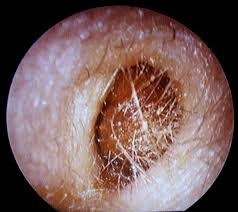

Le « bouchon d'oreille » désigne une accumulation de cérumen dans le conduit auditif.

Le bouchon de cerumen : Voici comment déboucher vos conduits et retirer un bouchon de cérumen sans risque. Une sensation d'oreille bouchée peut signifier la présence d'un bouchon de cérumen, très souvent chez l'enfant.

Enlever un bouchon dans l'oreille avec de l'eau tiède. Cette manière d'agir est assez simple, il vous faut tout d'abord une poire spéciale (certains conseillent une seringue mais c'est un peu plus difficile). Le bouchon de cire dans l'oreille, appelé également bouchon de cérumen, se produit lorsque le cérumen s'accumule dans votre oreille ou devient trop difficile à enlever naturellement.